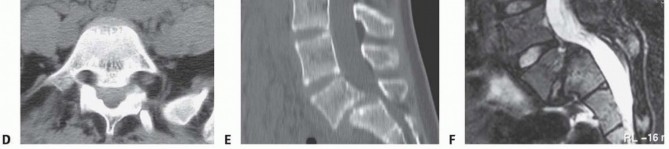

High-quality radiographs are taken immediately postoperatively to ensure proper graft and instrumentation placement before the patient is taken out of the operative room (

FIG 5

).

In the immediate postoperative period, the hips and knees are flexed and elevated using pillows to alleviate pain and immediate tension on the L5 root.

Pain control is instituted (eg, intrathecal analgesia and intravenous [IV] patient-controlled analgesia), and the patient is fitted with a thoracolumbosacral orthosis for comfort. The patient is then encouraged to stand and ambulate as tolerated. Postoperative posteroanterior and lateral standing spine radiographs are taken before discharge.

FIG 5 • Radiographs from a 17-year-old girl with high-grade isthmic spondylolisthesis who underwent decompression, reduction, and instrumented fusion. A,C. Initial PA and lateral radiographs showing the preoperative deformity. B,D. PA and lateral films showing postoperative correction using the CHOP technique.

*